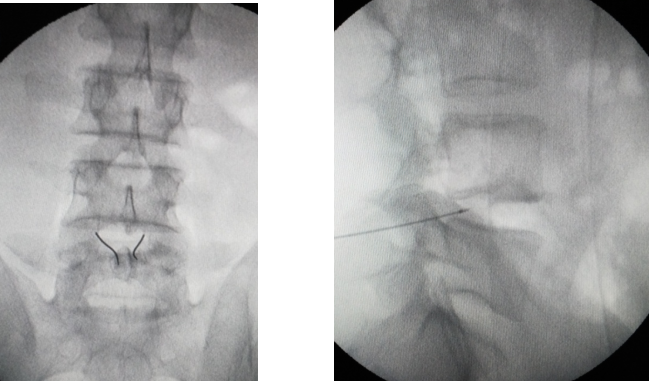

微创介入手术:

椎间盘内热损伤手术,包括椎间盘内电热疗法、射频热凝纤维环成形 术、双极射频髓核成形术。

机制:

- 局部加热使纤维环内的胶原纤维的三维螺旋结构的共价键破裂,胶原纤维变性收缩,从而封闭纤维环内小裂隙。

- 加热可以灭活椎间盘内炎症因子及降解酶,从而消除化学性致痛物质。

- 热能对椎间盘内疼痛感受器的破坏,使分布在纤维环外层的痛觉神经末梢灭活,使之失去接受和传递疼痛信号的能力。

- 热能可凝固分布于纤维环和后纵韧带上的神经纤维及椎间盘内的肉芽组织,改善椎间盘的炎性环境,减少刺激的传入。